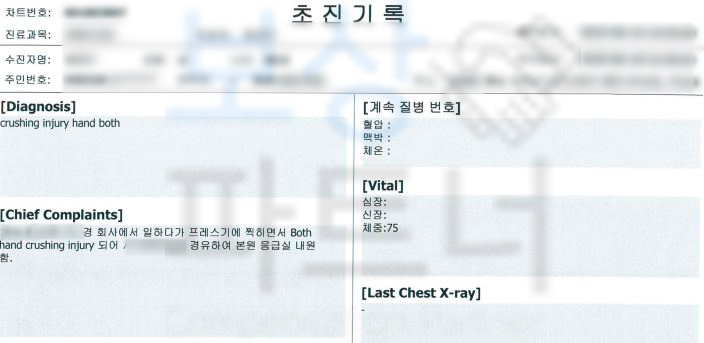

강@@님은 재해 당시 잔업 근무를 하던 날, 프레스 장비를 사용하던 중에 기계 오작동으로 인해 손가락이 으깨지는.. 사고를 당하셨습니다. 손가락의 상태는 심각했고 응급실 내원하여 수술을 받게 되었는데요, 수술을 실시하였음에도 손가락 으깸손상 s678 진단받아

강@@님은 손가락 일부가 절단될 수밖에 없었습니다. 산업 재해 근로자를 보호하기 위한 산재 보험을 통해 보상받을 수 있습니다.